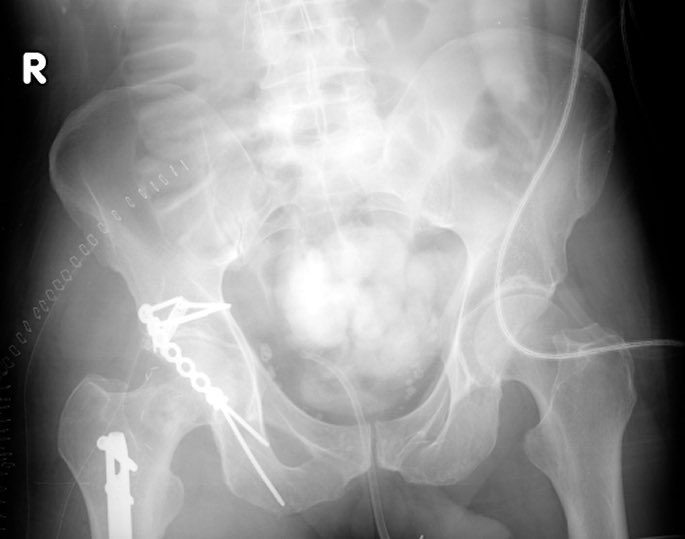

@drharpalselhi @centerofhip The hook name comes from the prongs that hold the reduced peripheral PW fragment-the spring name comes from the overcontou